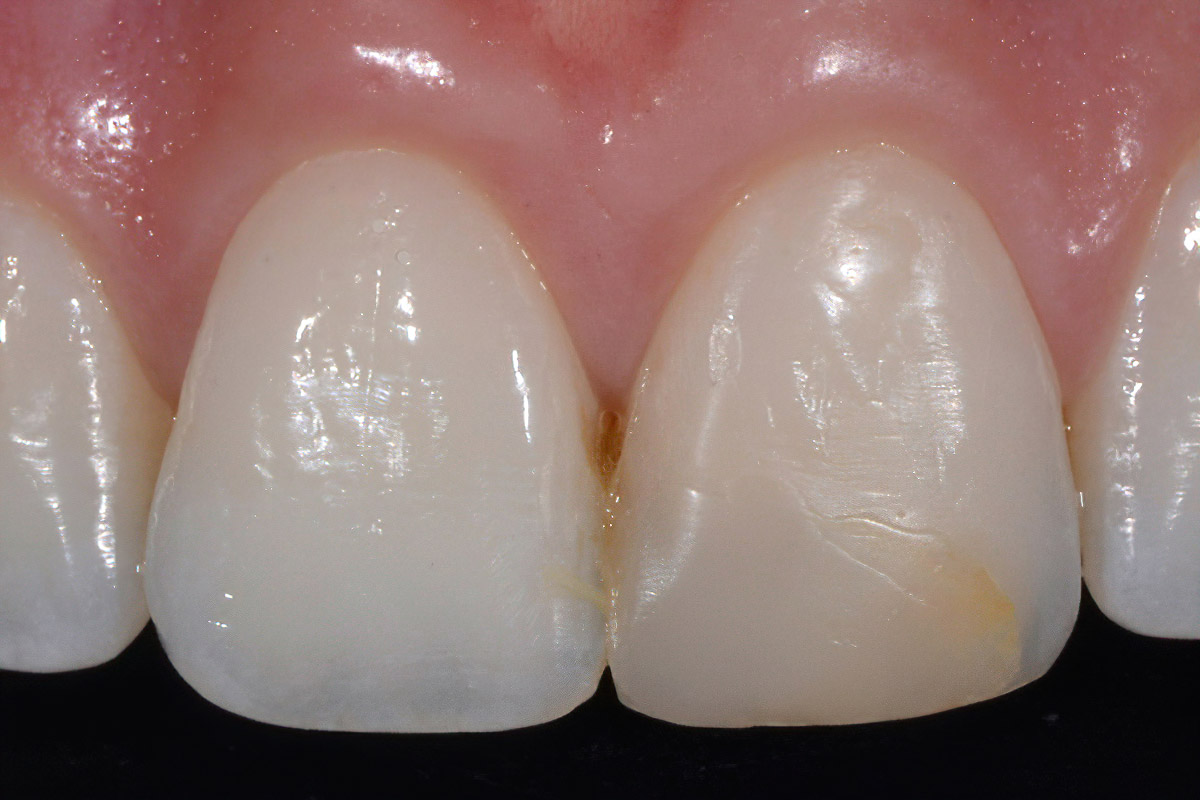

Anterior Case

Courtesy of Dr A. Mak, Australia